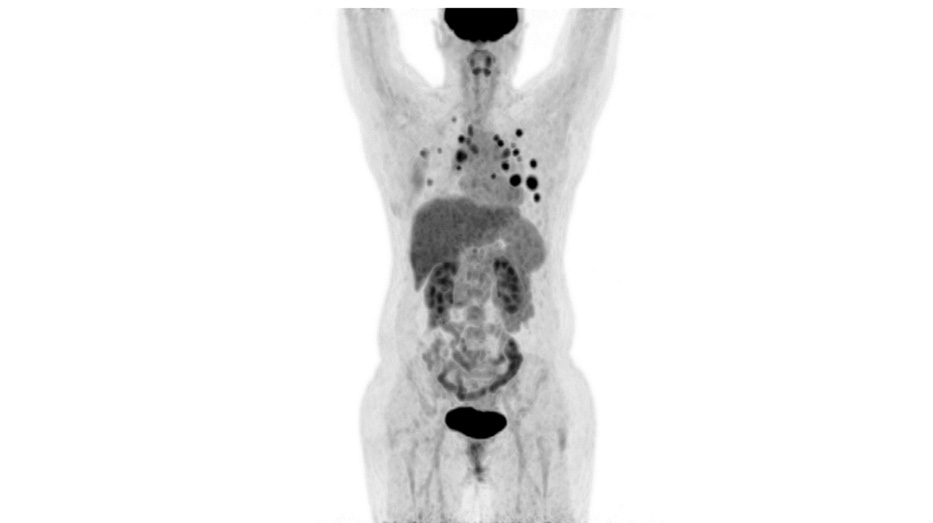

Пациентка №5 43 лет. Рак правой молочной железы, люминальный B, HER2-положительный (ИГХ 3+), исходно метастатический с января 2019 г. (кости, печень, легкие). Значимой сопутствующей патологии нет. Пациентка получила 5 линий лекарственной терапии с января 2019 по март 2022 г., включая все зарегистрированные на территории РФ анти-HER2-препараты – трастузумаб, пертузумаб, трастузумаб эмтанзин, лапатиниб. После 3 проведенных курсов терапии препаратом трастузумабом дерукстеканом зарегистрирован частичный ответ (90%) по критериям RECIST 1.1 (рис. 4, 5). Терапия продолжается по настоящее время, сохраняется частичный ответ. Отдельно следует отметить, что у данной пациентки по логистическим причинам терапия дважды прерывалась более чем на 1,5 мес, что в конкретном случае не повлекло за собой прогрессирования заболевания.

Рис. 5. Пациентка №5, ПЭТ КТ с 18-ФДГ, август 2022 г., после окончания терапии.

Fig. 5. Patient No.5, positron emission tomography with computed tomography with 18F-fluorodeoxyglucose; August 2022, after the therapy.